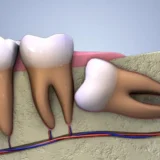

Răng số 8 hay còn được nhắc đến với tên gọi khác: răng khôn. Răng số 8 thường mọc rất muộn, không đóng góp được nhiều cho